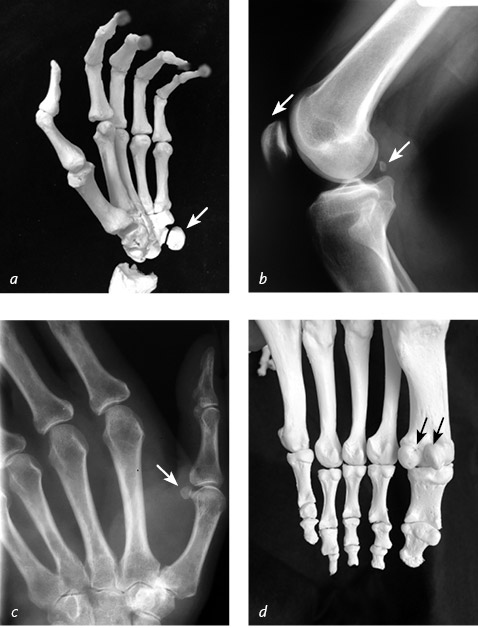

У некоторых птиц бедренные и плечевые кости полностью лишены костного мозга и являются важными элементами дыхательной системы: в их полости поступает воздух, который затем проходит через легкие и выдыхается. Аналогичные полые кости были и у некоторых динозавров – вероятно, тоже для содействия дыханию. Такое сходство в строении скелета доказывает, что современные птицы произошли от этих доисторических рептилий. Дотошные читатели могут поинтересоваться: «Раз вокруг губчатой костной ткани такой плотный цилиндр, как же в нее поступает кровь?» Если бы прямо через кость проходило отверстие для полноценных кровеносных сосудов, возникли бы проблемы: отверстие имело бы такие размеры, что нарушилась бы прочность конструкции и значительно снизилась бы ее способность сопротивляться сгибающим и скручивающим силам. В этом случае кости стали бы легко ломаться. Чтобы избежать этого, природа придумала хитрость: твердую оболочку кости пронизывает множество длинных, тонких, как иголочка, диагональных ходов. В каждом из них есть крохотная артерия и вена. В одних костях таких каналов для питательных веществ больше, в других – меньше. Тазовая кость и по одной кости запястья и лодыжки отличаются тем, что на крупных участках этих костей вообще нет таких отверстий. Из-за нехватки линий снабжения стройматериалами переломы там заживают плохо. ![]() В костях передней конечности белого носорога мы видим множество маленьких отверстий, через которые кровеносные сосуды подходят к внутренней губчатой костной ткани и питают ее Оклахомский городской музей остеологии, Оклахома, США Особо любопытные субъекты могут задуматься и о том, зачем нам в принципе нужны кости. Вспомним девиз департамента полиции Лос-Анджелеса: «Защищать и служить». Мы, хирурги-ортопеды, считаем, что эти ребята немного напутали – для нас служба идет перед защитой, – но нейрохирурги и кардиологи с нами не согласятся. Действительно, череп защищает мозг, а ребра и грудина оберегают различные внутренние органы, однако обслуживанием организма занимаются именно те крупные кости, за благополучие которых отвечают ортопеды: позвоночник, таз, конечности. Каждая кость имеет уникальную форму – такая особенность обеспечивает выполнение конкретных функций, одной из которых является защита нашего организма. ![]() Изменение скелета передних конечностей позволило разным животным приспособиться к выполнению определенных действий: выдерживать вес собственного тела, рыть, бегать, плавать, летать. Человеческая рука не идеальна для вышеперечисленных манипуляций, зато обладает большим преимуществом – способностью брать и удерживать инструменты Аналогичные кости у большинства млекопитающих, птиц и даже динозавров удивительно похожи по форме, хотя по размерам они очень сильно различаются между собой. Сравните, например, большеберцовую кость слона и куриную голень: обе кости узкие посередине и расширяются у коленного и голеностопного суставов. Широкие концы нужны для равномерного распределения нагрузки, а также для обеспечения достаточной площади крепления связок, которые не дают суставам болтаться. Если вас спросят, сколько в человеческом организме костей, пожалуйста, не называйте заученное число «двести шесть». Это самый популярный ответ – на самом деле все гораздо сложнее. Задумайтесь: люди отличаются друг от друга чертами лица, цветом волос, ростом, размером обуви. Под кожей мы такие же разные. Все имеет свои особенности: нервы, сухожилия, артерии, кости – их точное расположение и размер в моем организме мало что говорят о вашем организме. Чтобы решить головоломку с подсчетом костей, придется ответить на пять ключевых вопросов: «Кто?», «Что?», «Когда?», «Где?», «Зачем?». Во-первых, кто считает? Палеонтолог, смахивающий кисточкой песок с древнего скелета, может пропустить некоторые крохотные косточки. К ним относятся маленькие, погруженные в сухожилия сесамовидные кости [3], расположенные рядом с суставами по всему телу. Они названы так потому, что напоминают кунжутные зернышки. У человека эти кости крупнее (размером, скорее, с каперсы) и помогают равномерно распределить давление, когда мы берем что-нибудь руками или несем свой вес на ногах. У некоторых людей вообще нет сесамовидных костей в руках и ногах, а у кого-то их двадцать штук, однако эта особенность ни на что не влияет. Без сесамовидных костей можно обойтись (их даже называют добавочными), но почему бы не внести их в перечень костей в организме? Во-вторых, что считать костью? Коленная чашечка – это тоже гигантская сесамовидная кость, хотя ее всегда включают в любимое число «двести шесть». Как и запястную кость величиной с горошину. У большинства людей двадцать четыре ребра – по двенадцать с каждой стороны груди, но встречаются и такие индивидуумы, у которых двадцать шесть ребер, и медаль им за это не положена. Три крохотные косточки в каждом ухе учитываются, а вот сесамовидные кости стопы – нет, равно как и добавочные кости величиной с фасолину, располагающиеся вокруг бедра, колена и лодыжки. Когда мы считаем? У новорожденного ребенка около двухсот семидесяти костей, но со временем некоторые из них срастаются. Плоские кости черепа младенцев подвижны по отношению друг к другу – благодаря этому форма головы может меняться, что облегчает процесс родов, – но затем кости черепа соединяются, чтобы защитить мозг. В младенчестве кости запястья и лодыжек содержат мало кальция, поэтому пропускают рентгеновские лучи и не видны на снимках. Иногда кости запястья и лодыжек без особых причин объединяются с соседними костями, и это еще больше осложняет подсчет. ![]() Сесамовидные кости у основания ладони (a) и в передней части колена (b) включают в число «классических» двухсот шести костей организма человека, а сесамовидные кости задней части колена, большого пальца (c) и свода стопы (d) не учитывают Где мы ищем ответ? Разные книги дадут разные ответы на вопрос о количестве костей в организме человека. Все зависит от предполагаемой аудитории: в одних изданиях сесамовидные кости вообще не учитываются, а в других перечисляются все когда-либо описанные, до единой косточки. ![]() Число костей запястья не меняется в течение жизни, однако в младенчестве лишь две из них содержат достаточно кальция, чтобы проявиться на рентгеновском снимке (a). Через шесть лет в идентичной проекции видны уже семь из восьми костей (b). И наоборот, число костей черепа уменьшается: у младенца (c) их больше, чем у взрослого (d), так как они частично срастаются по мере взросления |